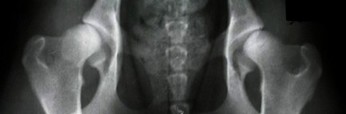

A - stawy biodrowe normalne

B - stawy biodrowe prawie normalne i bardzo nieznaczne odchylenie od normy, ale pozwalające na rozpoznanie schorzenia

C - dysplazja nieznaczna i niebudzące wątpliwości, wyraźne odchylenie od normy

D - dysplazja częściowa tzw. ograniczona gdzie wyraźnie rozpoznaje się nadwichniecie będące wynikiem dysplazji

E - dysplazja ciężka gdzie płaska, pozbawiona jej eliptycznego lub kulistego kształtu panewka występuje z przemieszczeniem głowy kości udowej.

W przypadku stwierdzenia odchylenia na jednej panewce podaje się za wynik gorszą panewkę:

czyli w tym przypadku E ( 4,1 )